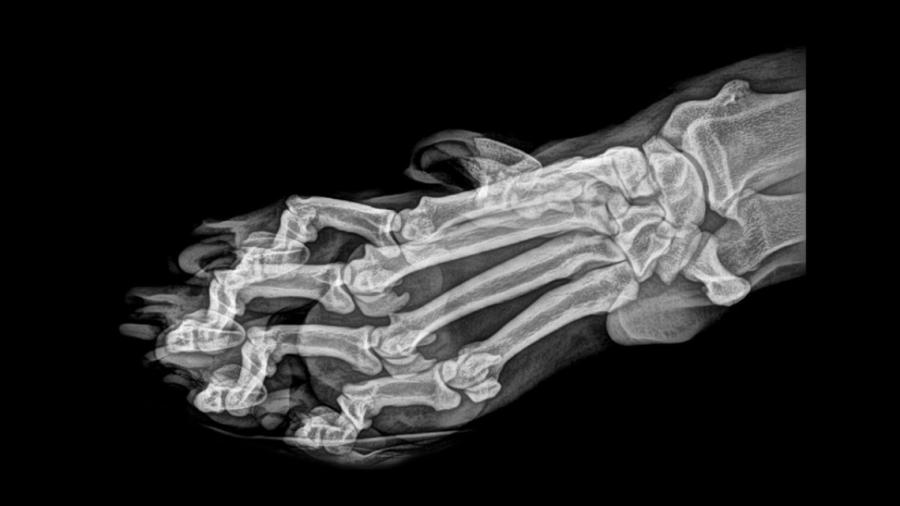

A pocos días de Halloween, el zoológico de Oregón, en Estados Unidos, decidió compartir hace unos días las imágenes hechas en rayos X de sus animales.

Las radiografías fueron hechas durante las inspecciones de salud rutinarias, por lo que en ninguna muestra a un animal enfermo o lastimado.

La institución indicó que los animales reciben a menudo, exámenes de salud de rutina.